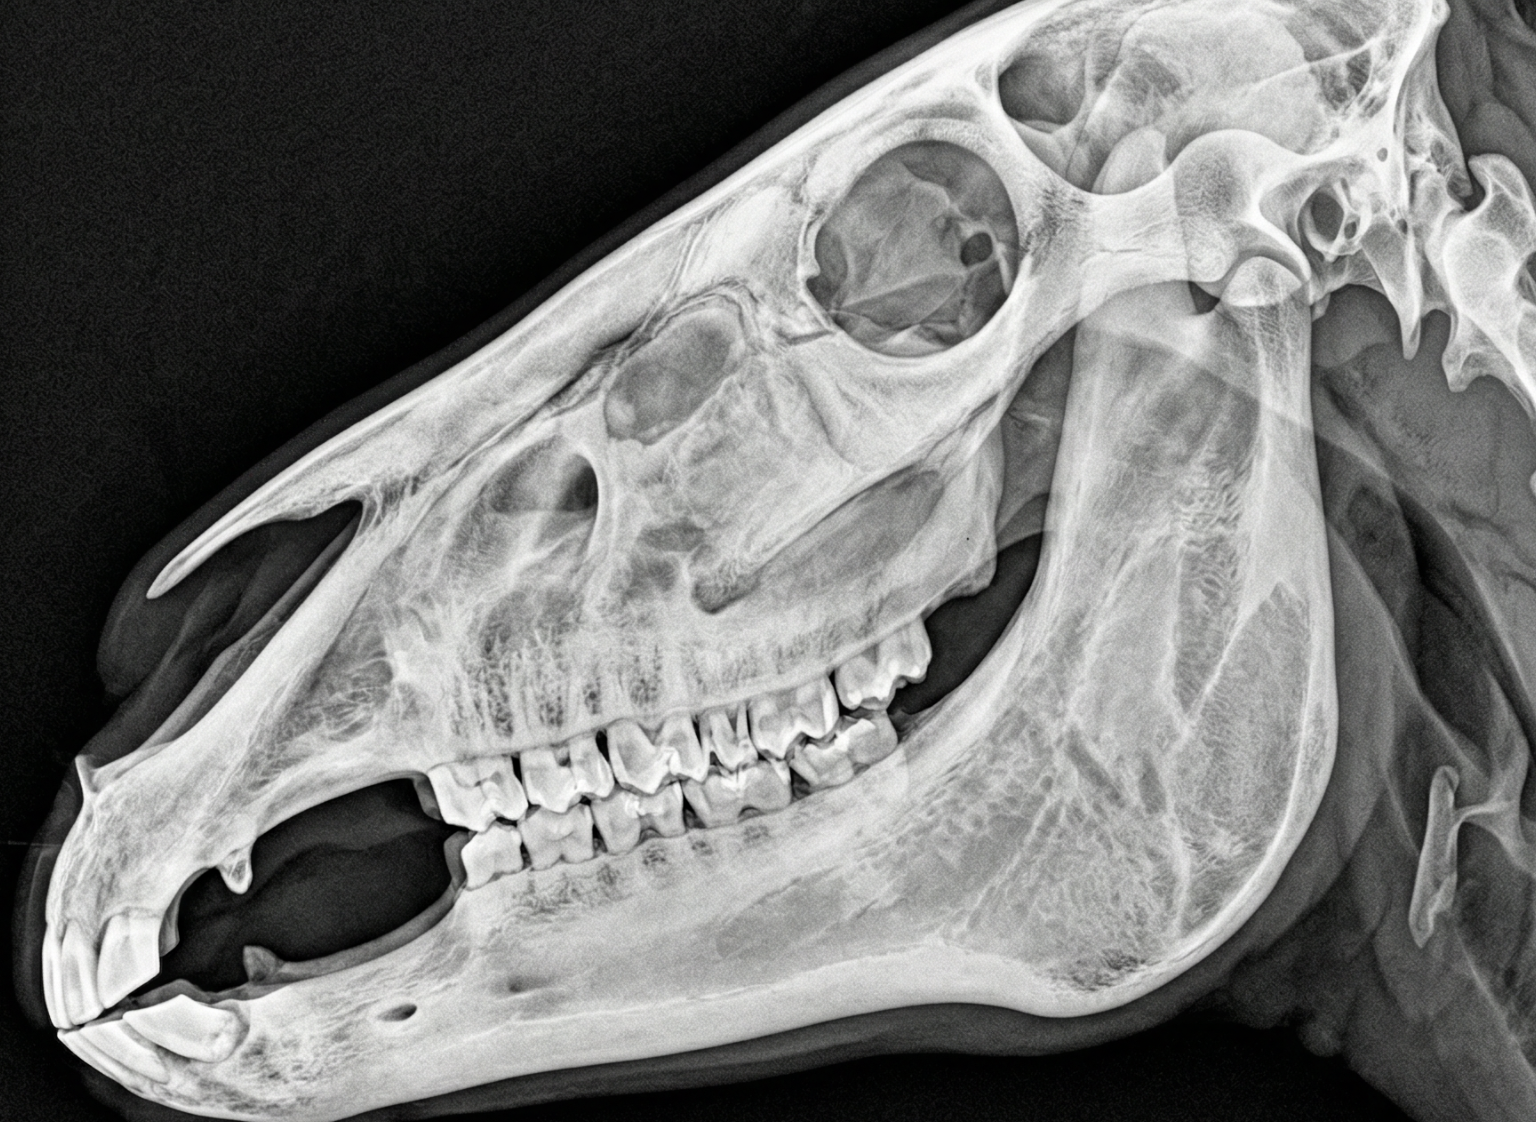

Tierart wählen

Hund, Katze, Pferd, Rind oder Exoten. Region: Thorax, Abdomen, Extremitäten, Schädel.

Animioo erkennt über 80 Befundmuster — von der Lobärpneumonie beim Hund bis zum Hufgelenk-Arthrosegrad beim Pferd.